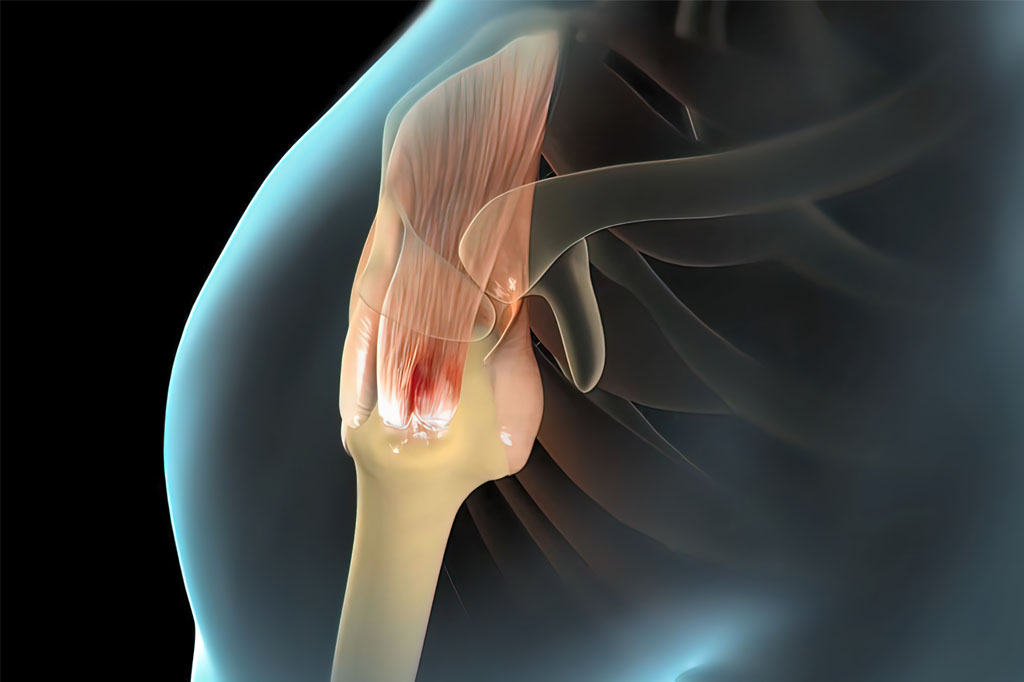

Rotátor köpeny szakadás

A rotátor köpeny a vállizület stabilizálásában és mozgatásában kap szerepet. 4 különböző izom köpenyszerűen körbeveszi a felkarcsont fejét.

Egy dinamikusan, jól működő rendszer, amely minden mozgásfázisban stabilizálja és lehúzza felkarcsont fejét, a vállizületet és lehetővé teszi a rendkívül szabad mozgást és stabilitást. Ennek a rendszerek a megbomlása a válltáji fájdalmak egyik leggyakoribb oka a biceps ín gyulladásos, degeneratív megbetegedései mellett. Ez a sérülés létrejöhet sportolóknál, fizikai munkásoknál, de a kor előre haladtával is növekszik a számuk.

A rotátor köpeny a vállizületet körülvevő 4 izomból álló köpenyszerű képlet, amely a felkarfejet a vállizület közepén tartja minden mozgás alkalmával, a váll emelésében és forgómozgásokban segít.

A rotátor köpeny felett a lapocka egy nyúlványa (acromion) helyezkedik el nagyon közel, a kettő között csak egy vékony zselés anyaggal töltött nyáktömlő helyezkedik el. Ez a tömlő csökkenti a súrlódást a két felszín közt a kar mozgása közben.